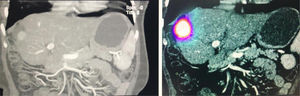

Inclusion criteria: cirrhotic patients of any etiology, with a diagnosis of HCC stage B, Child Pugh A and B with 7 points, who had previously undergone a morphological study (CT / MRI) and arteriography to characterize the lesion, to know the irrigation of the tumor and rule out extrahepatic shunts that contraindicate the application of RE-Y90. Subsequently, the procedure was simulated with MAA-Tc99m in order to record its distribution, perform dosimetry, and on the day of RE-Y90, an image study was performed with PET / CT in order to verify the distribution. Exclusion criteria. Patients with liver cirrhosis of any etiology with BCLC Stage B of the Child Pugh B plus 7 points or those with Child Pugh A or B 7 points with extrahepatic shunts. Do not accept this type of therapy. Patients who were not candidates for this therapy were sessioned at the Gastrointestinal and Liver Tumor Meeting to decide their treatment. Response to treatment at 3 and 6 months was analyzed using the mRECIST criteria, progression-free time at 6 months, and adverse effects were recorded.

Control Computed Axial Tomography was performed with good response, without disease progression at 3 and 6 months, asymptomatic.